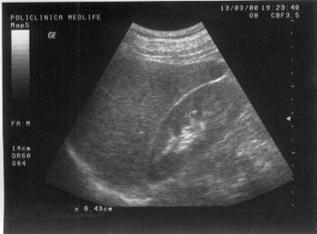

Figura

13. Ovarul st`ng este ]nlocuit de o formaiune complex[, transsonic[ =i

solid[. Partea solid[ ]n proporie de 40%, cu ecostructura hiperecogen[

este dispus[ sub forma de prelungiri papilifere cu contur neregulat =i

prezint[ ]n interior c`teva mici zone transsonice (posibil arii de

necroz[). Aspectul sugereaz[ chistadenocarcinom ovarian.